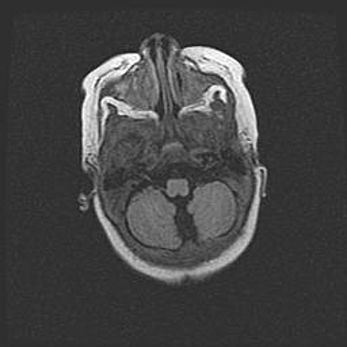

Подострая гематома правой гемисферы мозжечка.

Наружная гидроцефалия.

Возраст: 15 дней

Вес: 3100 г

Пол: женский

Окружность головы: 37 см

Срок гестации: 35-36 недель

При открытой наружной форме гидроцефалии у новорожденных расширяются и переполняются субарахноидные пространства.

Кровоизлияния в мозжечок имеют две клинико-анатомические формы: полушарные гематомы и кровоизлияния в червь.

К появлению этой патологии может привести: повреждения головного мозга, возникающие в результате асфиксии и гипоксии плода при беременности, или травмы во время родов. Редко гематома мозжечка может быть результатом первичной коагулопатии и сосудистой мальформации, диссеминированном внутрисосудистом свертывании, изоиммунной тромбоцитопении.